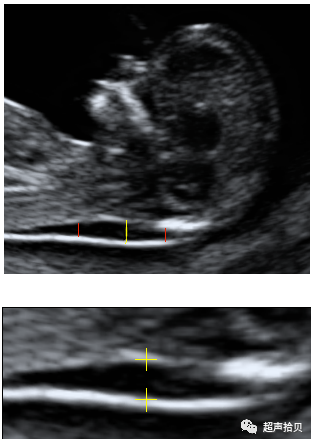

测量NT的最佳孕周是:11+0~13+6周。测量时,头臀径(CRL)应在45mm~84mm之间。

放大图像直至胎儿头部和上半胸占据整个屏幕

必须获得胎儿正中矢状切面。

胎儿应处于自然姿势,头与脊柱成一条直线。当胎儿颈部过于伸展,测量值会错误地增加;当颈部过于屈曲,测量值会错误地降低。

必须小心鉴别胎儿皮肤和羊膜。

测量NT最宽处

• 测量应在两个游标尺水平线的内缘进行。将游标尺放在颈项透明层两侧边界线内侧“上”。游标尺的交叉点应与白色边界线融合,难以看见,而不是将其置于颈项部皮下的液体中;

• 在放大图像的时候,降低增益(gain)非常重要。这样可以防止将游标尺置于白线的模糊部分,否则容易造成错误地低估颈项透明层厚度;

• 超声扫描过程中,需多次测量,取符合上述标准的最大测量值,输入数据库。